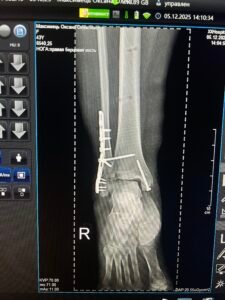

Лікування було проведено в декілька етапів. Оскільки у пацієнтки при огляді діагностовано септичну нестабільність металофіксаторів, хронічний остеомієліт великого мілкової кістки та стійку еквіно-варусну деформацію стопи(“кінська стопа”) першим етапом виконано видалення пластини, санація рани та позавогнищевий остеосинтез апаратом Ілізарова. Другим етапом виконано перемонтаж АЗФ та поступова керекція еквіно варусної деформації стопи в апараті Ілізарова.